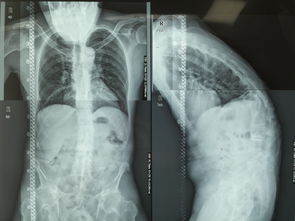

近期,一些宣称能治愈强直性脊柱炎的“祖传秘方”风湿透骨丸在网络上悄然流传,引发了医药监管部门和患者群体的高度关注。强直性脊柱炎作为一种慢性自身免疫性疾病,其治疗需要长期规范管理,而所谓的“特效药”往往隐藏着巨大的健康隐患。

强直性脊柱炎的治疗应当遵循科学规范。正规医疗机构通常采用非甾体抗炎药、生物制剂等经过严格临床试验的治疗方案,这些方法虽然不能彻底治愈疾病,但能有效控制病情进展,提高患者生活质量。